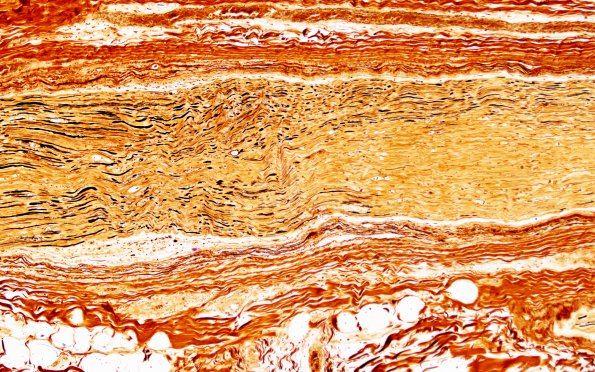

2D3,4 The longitudinal fascicle showing patchy intrafascicular axon loss. (Bielschowsky silver stain)